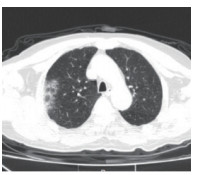

2.5 胸部CT结果入院时,为所有患者进行了胸部螺旋CT检查,47例(71.2%)患者表现为双侧多发性斑片样和磨玻璃样混浊,典型影像学表现见图 1,19例(28.8%)患者表现为单侧肺炎,典型影像学表现见图 2。

| 图 2 单肺感染 Fig 2 Single lung infection |

在入院治疗3 d后,再次对所有患者复查了胸部螺旋CT。39例(59.1%)患者肺部感染灶有不同程度增多,27例(40.9%)患者肺部感染灶无明显进展。